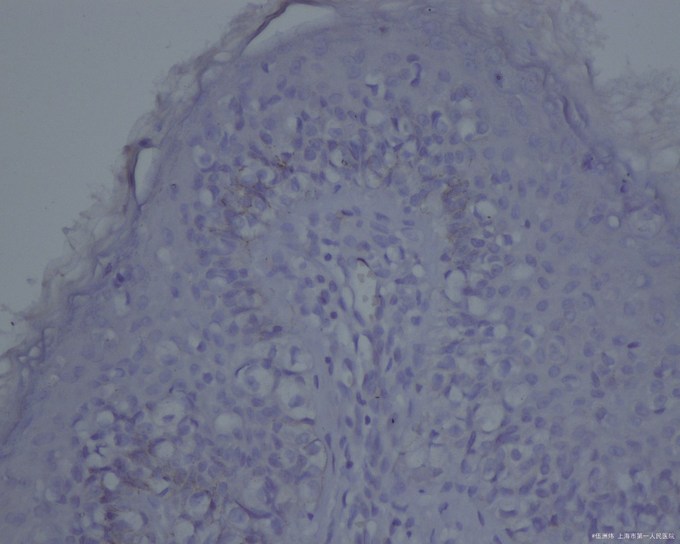

表皮内有不等量的Paget细胞,有时可见核被挤压在细胞的一边呈印戒状。在表皮附属器,特别是毛囊或外泌汗腺导管的上皮内也能见到Paget细胞,并能侵犯真皮,这与乳房Paget病不同。乳房外Paget病的Paget细胞含涎粘蛋白、耐淀粉酶和耐透明质酸酶,故对PAS、阿新蓝(pH 2.5)可呈阳性。免疫组化显示Paget细胞对癌胚抗原、顶泌汗腺上皮抗原均呈阳性,雌激素受体和孕激素受体阳性者较低,与乳房Paget病明显不同

原因 原发性乳房外Paget病的起源目前仍有争论,以往认为Paget细胞来源于汗腺癌沿导管上皮向表皮蔓延,但发现表皮及附属器的病变为多灶性起源,真皮内浸润来自表皮而非导管及腺体结构。免疫组化结果支持顶泌汗腺起源,推测它可能起源于顶泌汗腺导管开口部细胞,或是表皮内向顶泌汗腺分化的多潜能细胞。继发性乳房外Paget病的表皮病变常由深部直肠、子宫颈或膀胱癌扩展而来。 病理生理变化 表皮内有不等量的Paget细胞,有时可见核被挤压在细胞的一边呈印戒状。在表皮附属器,特别是毛囊或外泌汗腺导管的上皮内也能见到Paget细胞,并能侵犯真皮,这与乳房Paget病不同。乳房外Paget病的Paget细胞含涎粘蛋白、耐淀粉酶和耐透明质酸酶,故对PAS、阿新蓝(pH 2.5)可呈阳性。免疫组化显示Paget细胞对癌胚抗原、顶泌汗腺上皮抗原均呈阳性,雌激素受体和孕激素受体阳性者较低,与乳房Paget病明显不同。 症状体征 本病大多好发于男性,女性少见。常发生于50岁以上,病程缓慢,病期半年至十多年。其损害好发于顶泌汗腺分布部位,如阴囊、阴茎、大小阴唇和阴道,少数见于肛周、会阴或腋窝等处。大多为单发,少数多发,同时发生于两个部位者更少见,极少数患者可伴发乳房Paget病。乳房外Paget病可继发于腺癌的扩展,如从直肠到肛周区,从宫颈到女阴区,从膀胱到尿道、龟头或腹股沟区等。另一方面,长期在生殖器部位的乳房外Paget病可侵犯宫颈或泌尿道。损害如同乳房Paget病,呈界限清楚的红色斑片,大小不一,边缘狭窄,稍隆起,呈淡褐色,中央潮红、糜烂或渗出,上覆鳞屑或结痂,有时呈疣状、结节状和乳头瘤状,自觉有不同程度的瘙痒,少数有疼痛。 诊断检查 对50岁以上老年人发生在外生殖器部位或肛周长期不愈的湿疹样皮肤损害,特别是边缘明显者,应提高警惕,活检可以明确诊断。 治疗方案 首选手术切除,可用Mohs外科技术。若损害较大,累及腹股沟和肛周时,需作植皮术。继发性乳房外Paget病应对原发病作相应处理。复发病例可再次手术切除。